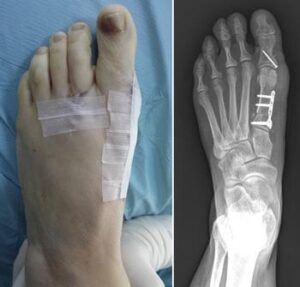

Because bunions vary in shape and size, there are different surgical procedures performed to correct them. In most cases, bunion surgery includes correcting the alignment of the bone by cutting and shifting the bones. This will most likely require the placement of surgical hardware (plates and screws) as well as repairing the soft tissues around the big toe. Your doctor will talk with you about the type of surgery that will best correct your bunion.

An osteotomy is a surgical procedure in which your doctor makes precise cuts in the bones to realign the joint and correct the bunion deformity. After cutting the bone, the newly adjusted position is stabilized using pins, screws, or plates. This realignment ensures the bones are straighter and the joint is properly balanced.How Osteotomy Works

In this procedure, which is also called a fusion, your doctor removes the arthritic joint surfaces, then inserts screws, wires, or plates to hold the surfaces together until the bones heal.Arthrodesis is commonly used for patients who have severe bunions and/or severe arthritis, and for patients who have had previous unsuccessful bunion surgery.

Depending on your bunion and the procedures you need, your doctor will make an incision along the inside of your big toe joint or on top of the joint. In some cases, more than one incision is needed to correct the bunion deformity.

You will be discharged from the hospital with bandages holding your toe in its corrected position. Because keeping your toe in position is essential for successful healing, it is very important to follow your doctor's directions about dressing care. Do not disturb or change the dressing without talking to your doctor. Interfering with proper healing could cause the bunion to come back.

Your sutures (stitches) will be removed about 2 weeks after surgery, but your foot will require continued support from dressings or a brace for 6 to 12 weeks.